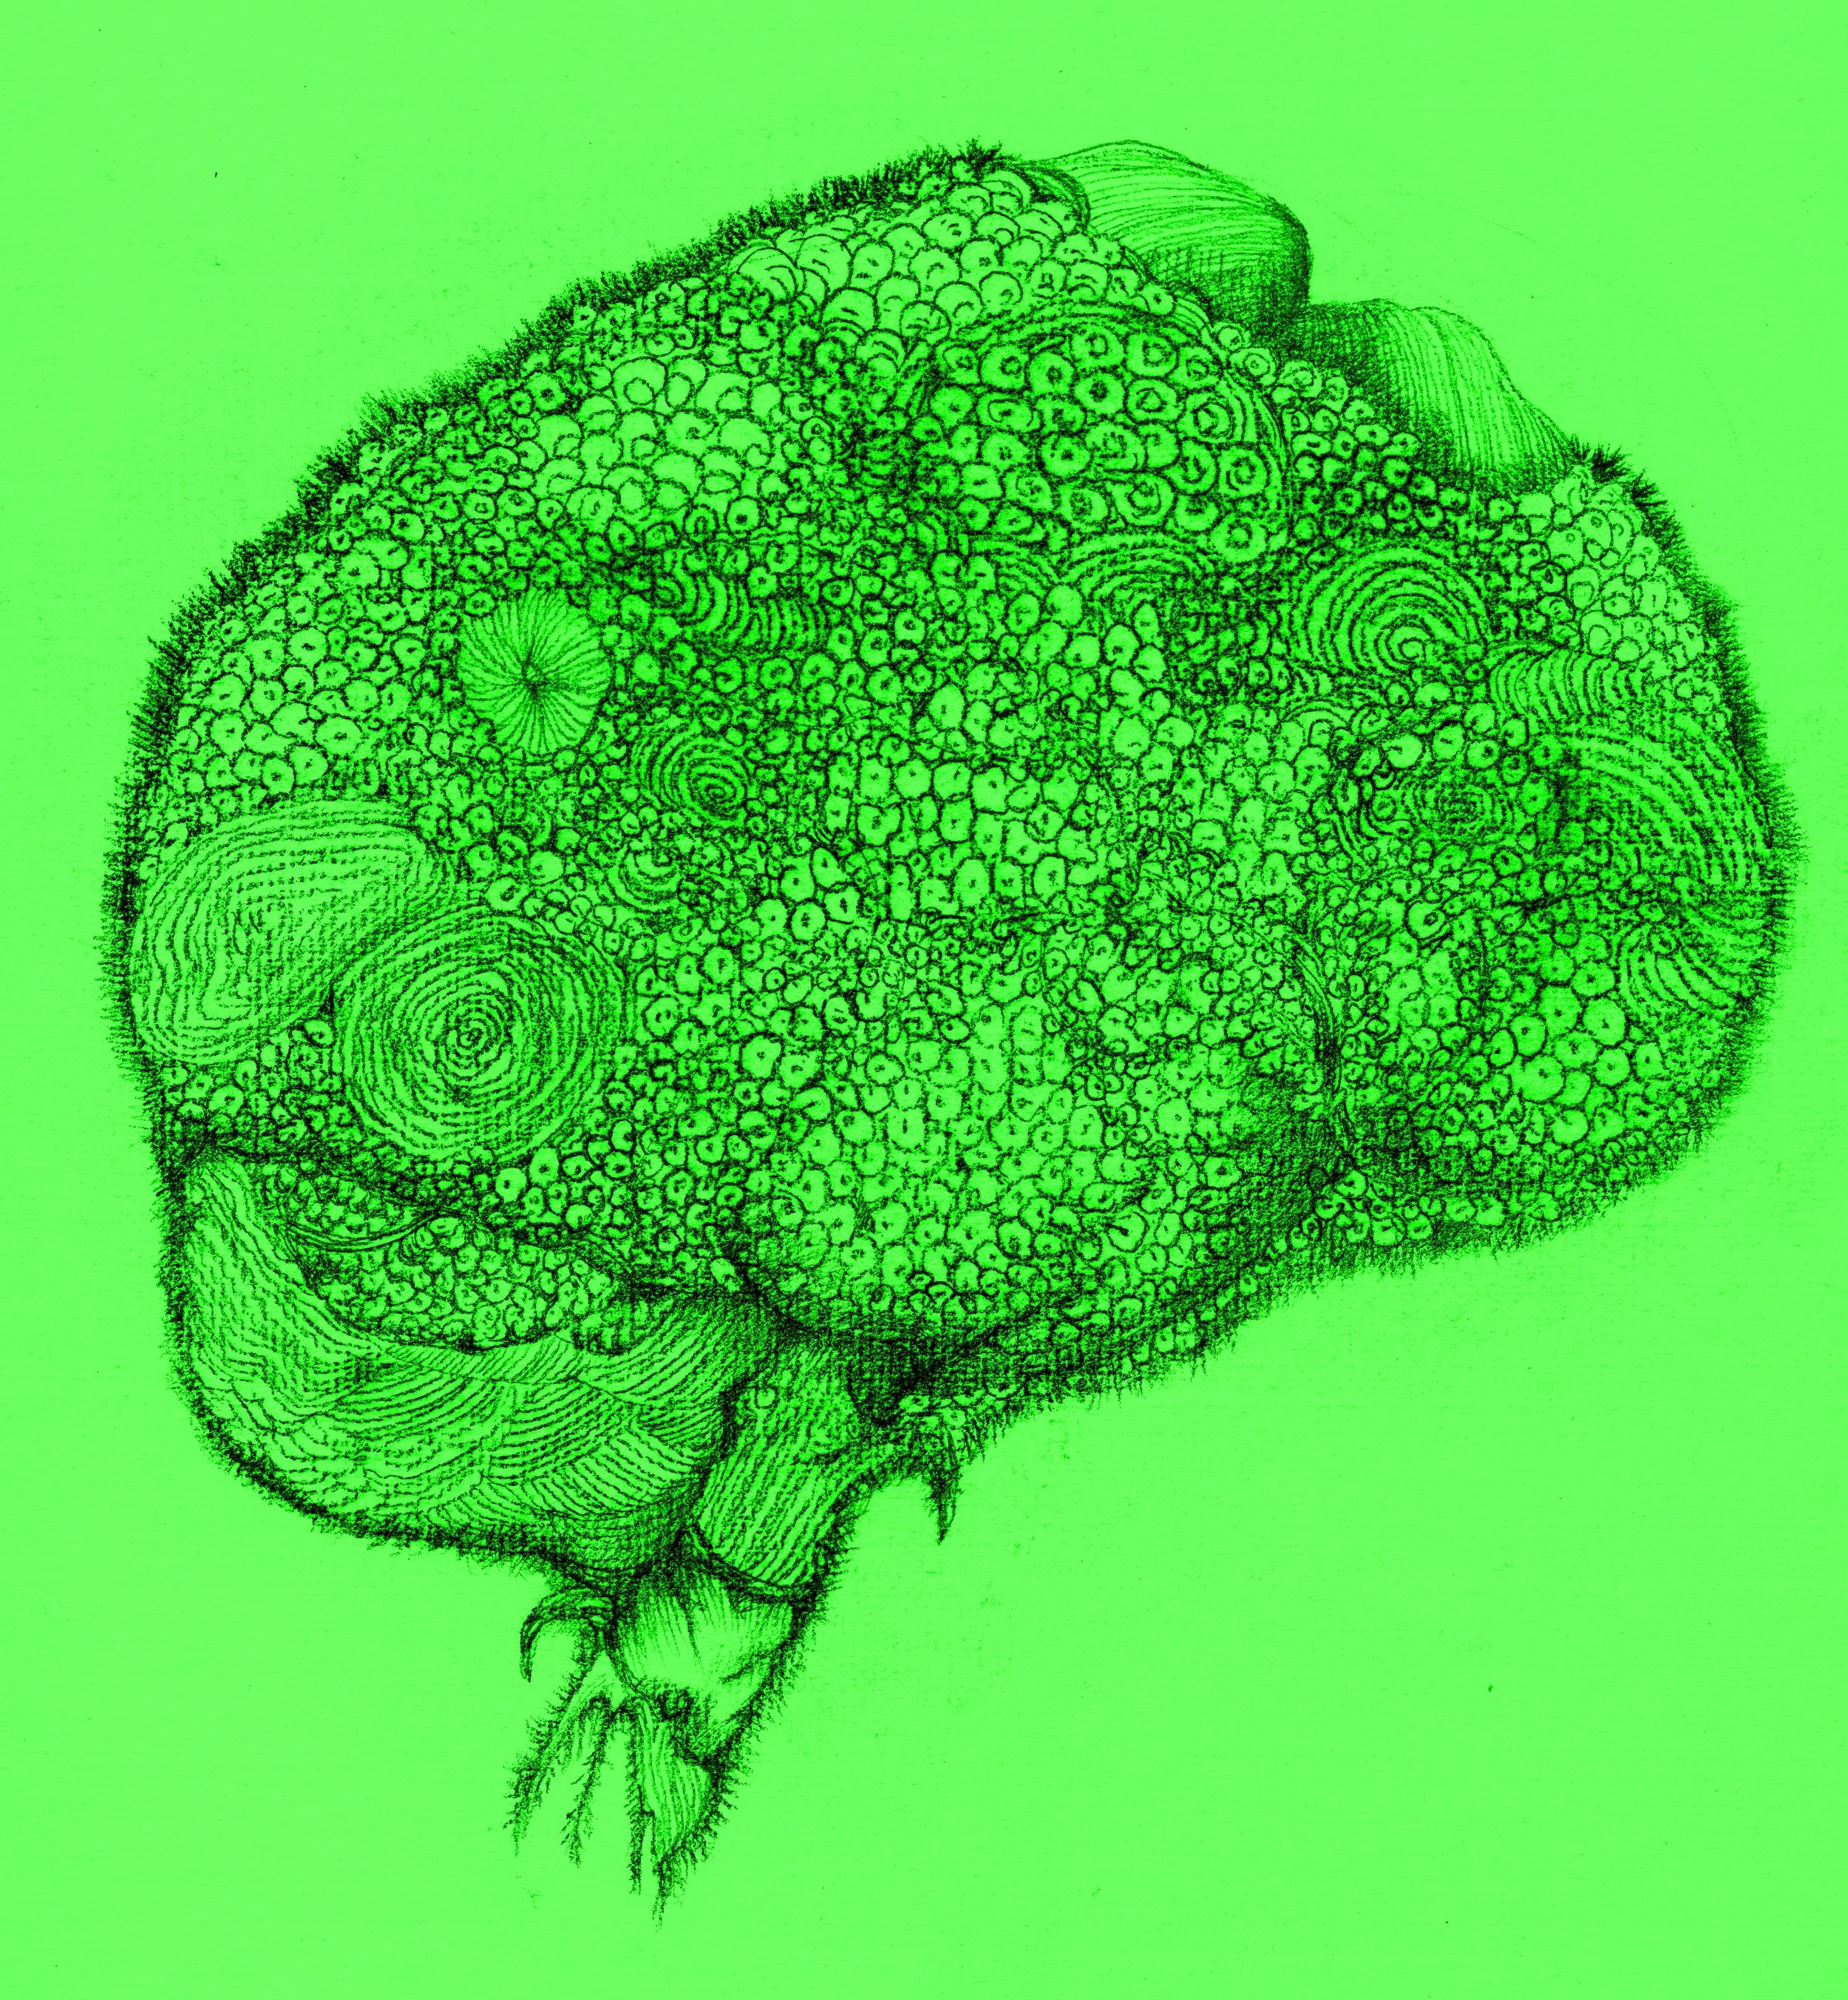

Brain-burning (燒腦)

腦梗(Cerebral infarction)

Vegetative Brain (植腦)

Brain Fog 1 (腦霧)

Brain Fog 2(腦霧)

Brain Fog 3 (腦霧)

Brain Fog 4(腦霧)

Brain Fog 5 (腦霧)

Brain Fog 6(腦霧)

Brain Fog 7(腦霧)